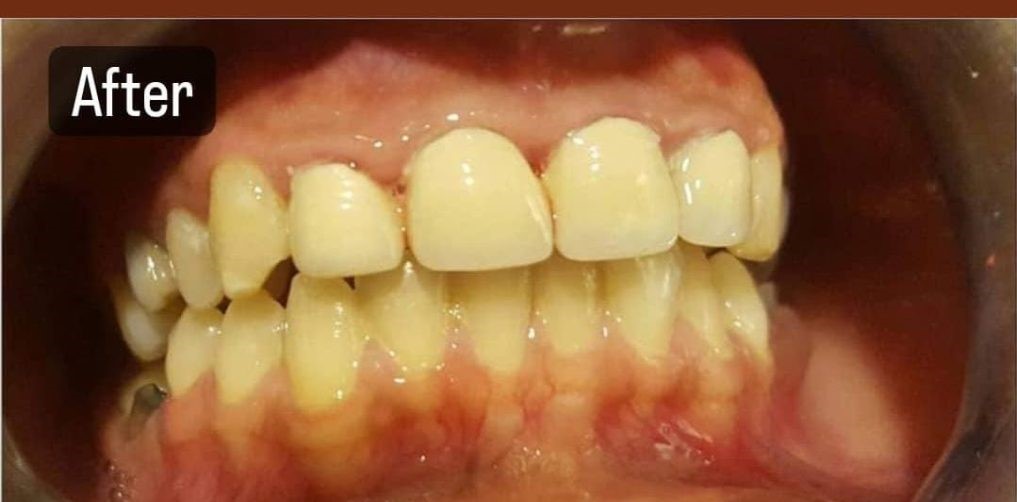

After complete healing, a custom-designed crown is securely placed, matching your natural teeth in shape and color. The result is a strong, natural-looking smile restored with precision and care.